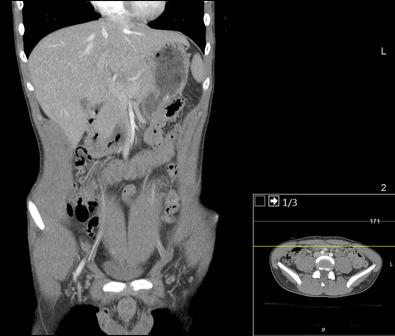

The Computer Tomography (CT) scan represents a widely used and valuable imaging diagnostic tool in modern medicine It enables medical professionals to detect the presence of tumors, traumatic injuries, hemorrhages, and a range of other health abnormalities (Computed Tomography (CT), 2022)

The technique uses a rotating X-ray beam around the patient to generate cross-sectional images, which are then processed and subsequently stacked to create a 3D image However, the procedure requires exposure to ionizing radiation, which poses a potential threat to DNA Ionizing radiation can lead to single-stranded and doublestranded DNA breakages, which may lead to mutations and, ultimately, to cancer. Although the radiation doses used in CT scan procedures are considered generally safe, concerns have been raised regarding children, who are more susceptible to the harmful effects of ionizing radiation, as well as those patients who undergo repeated exposures

Similarly, Miglioretti et al identified an elevated risk of radiation-induced cancer in children undergoing pediatric CT imaging Miglioretti et al conducted a retrospective observational study using data from over seven US healthcare systems from 1996 – 2010, including children younger than 15 years old who were examined via CT scans (152,419 – 371,095 children per year) The study found that cancer risks varied based on age, gender, and the region of the body being imaged Younger patients and girls exhibited an increased risk for solid cancer (projected cases: 13 1 – 33 9 girls vs 6 3 – 14 8 boys per 10,000 CT scans). Furthermore, abdomen/pelvis CT scans, which have a mean effective dose of 10 6 millisieverts (mSv) (same as 10 6 mGy) in children younger than 5 and 14 8 mSv in children 10-14 years old, had the highest risk for radiation-induced solid cancers, especially in the older children

Meanwhile, head CT scans, the most commonly performed pediatric CT, posed a higher risk of leukemia and brain cancer, particularly in children under five years old, which had a projected risk of 1 9 cases of leukemia per 10,000 head CT scans The study projected that four million pediatric CT scans of the head, abdomen/pelvis, chest, or spine in the US per year could cause 4,870 future cancers The majority of projected cancers in exposed girls are breast, thyroid, lung cancer, and leukemia, whereas in exposed boys, about half the projected cancers are in the brain, lung, colon cancer, and leukemia Given that effective doses vary between 0.03 – 69.2 mSv, reducing the highest effective doses (25% upper quartile) might aid in potentially preventing over 43% of the projected cancers (Miglioretti et al , 2013) These projections highlight the potential longterm consequences of radiation exposure from CT imaging pediatric patients Healthcare providers should carefully consider the benefits and necessity of these procedures, especially in the pediatric population, which displays the highest vulnerability to the effects of ionizing radiation due to their sensitivity and longer lifespan to develop cancer.

Figure 2: https://upload wikimedia org/wikipedia/commo ns/f/f5/CT of a normal abdomen and pelvis%2 C coronal plane 44 png